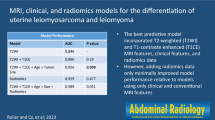

Four qualitative MR features most strongly associated with LMS were nodular borders, haemorrhage, “T2 dark” area(s), and central unenhanced area(s) (p ≤ 0.0001 each feature/reader). The highest sensitivity [1.00 (95%CI:0.82-1.00)/0.95 (95%CI: 0.74-1.00)] and specificity [0.95 (95%CI:0.77-1.00)/1.00 (95%CI:0.85-1.00)] were achieved for R1/R2, respectively, when a lesion had ≥3 of these four features. Sixteen texture features differed significantly between LMS and ALM (p-values: <0.001-0.036). Unsupervised clustering achieved accuracy of 0.75 (sensitivity: 0.70; specificity: 0.79).

Combination of ≥3 qualitative MR features accurately distinguished LMS from ALM. TA was feasible.

• Four qualitative MR features demonstrated the strongest statistical association with LMS.

• Combination of ≥3 these features could accurately differentiate LMS from ALM.

• Texture analysis was a feasible semi-automated approach for lesion categorization.